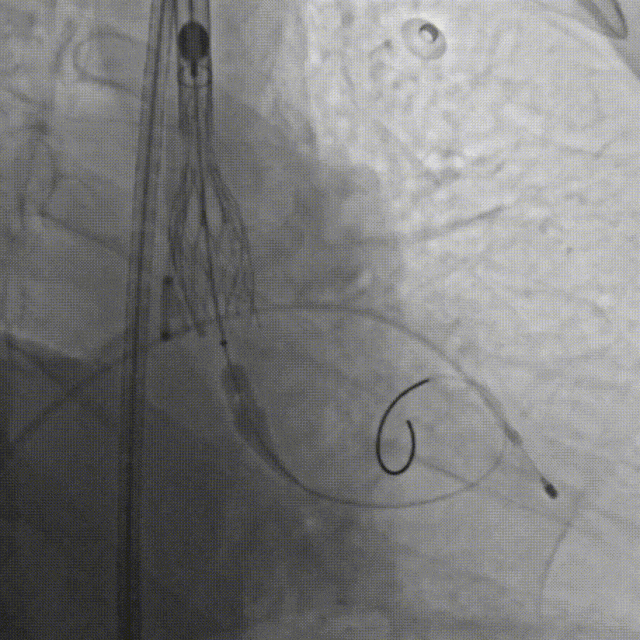

手术当日,在多学科团队的紧密监控与配合下,首先由心脏重症监护科蓝新平主任团队顺利建立VA-ECMO(图C),为患者筑起了坚实的“生命之桥”。随后,钟炜教授手术团队在影像学的精准引导下,凭借娴熟技术及团队默契配合,通过血管路径将人工瓣膜输送至心脏预定位置,一次精准释放,即刻解除了“心门”的梗阻(图D--G)。整个手术过程中,ECMO运行平稳,患者生命体征始终保持稳定,未出现预期中的血流动力学剧烈波动及消化道出血加重的情况,顺利完成手术操作。

D.成功跨瓣后行球囊扩张

E.行主动脉根部造影,精准定位

F.缓慢、平稳、逐步释放瓣膜支架

G.瓣膜支架成功释放